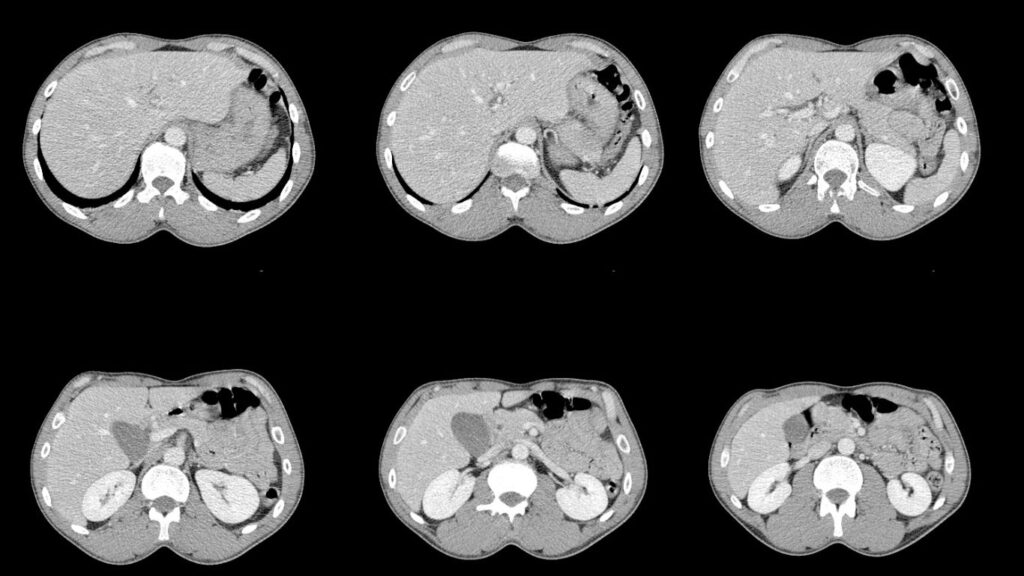

Tomografía para Detectar Cáncer: Precisión en Querétaro

En Altaria, entendemos la importancia de una detección temprana para el diagnóstico de cáncer. Nuestra tecnología de tomografía avanzada nos permite ofrecer un enfoque integral y preciso en la obtención de imágenes médicas. Sabemos que la salud de nuestros pacientes es primordial, por lo que garantizamos rapidez y confiabilidad en nuestros servicios de tomografía para […]